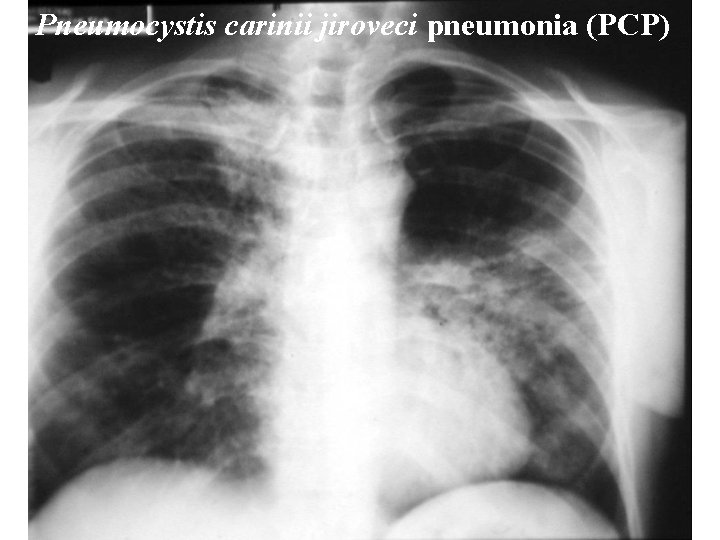

Pneumocystis carinii jiroveci pneumonia (PCP) Pneumocystis carinii jiroveci pneumonia

PCP – High-resolution CT scan (EP 20. 11. 2014) n showing ground-glass appearance. CT (HRCT) scan i 32 -year-old man with HIV infection showing ground-gdue to Pneumocystis carinii pneumonia. CD 4+ lymfocyty 4/µl, MI…………. . IF……… n Jirovecii ˃ 100 000 kopií DNA/rekaci n